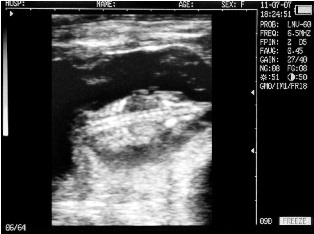

Ultrasound images of cows reproductive system, generated by a scanner Sonovet with rectal linear transducer.

Filled bladder cow